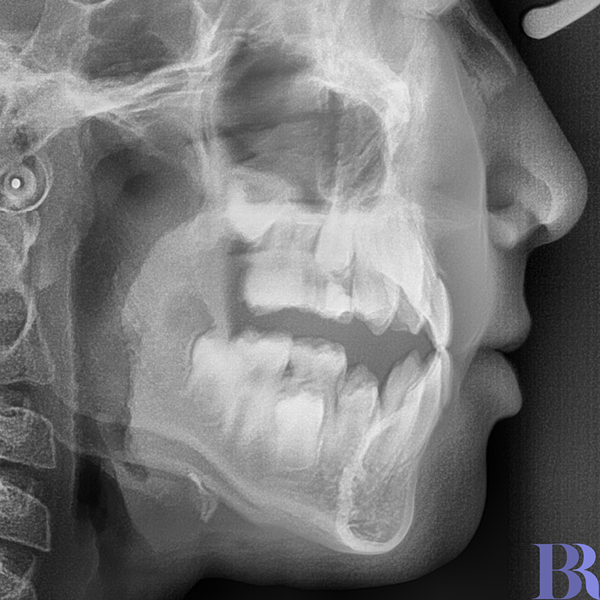

위의 엑스레이처럼

앞니끼리 맞닿게 물 수 있다면

교정만으로 반대교합을

해결하실 수 있습니다.